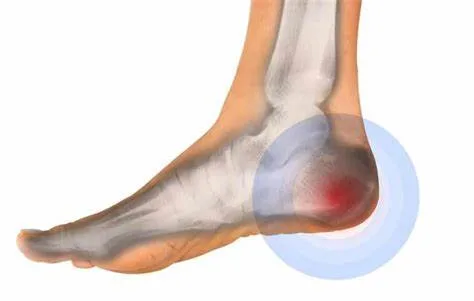

تم طرح طريقة علاج الشوكة العظمية بالأعشاب وكيفية التخلص من آلامها على موقع إيجي بلوج نيوز. يُعاني العديد من الأشخاص من أعراض الشوكة العظمية، مثل الشعور بالألم في الكعب أو في منتصف القدم، وقد يتفاقم هذا الألم مع مرور الوقت.

تعتبر الشوكة العظمية واحدة من الأمراض التي تصيب العديد من الأفراد وتسبب لهم الآلام في بعض المناطق في الجسم، ولكن من حسن الحظ أن هناك الكثير من الطرق العلاجية التي تم توافرها لعلاج الشوكة العظمية أو حتى التخفيف من أعراضها المزعجة.